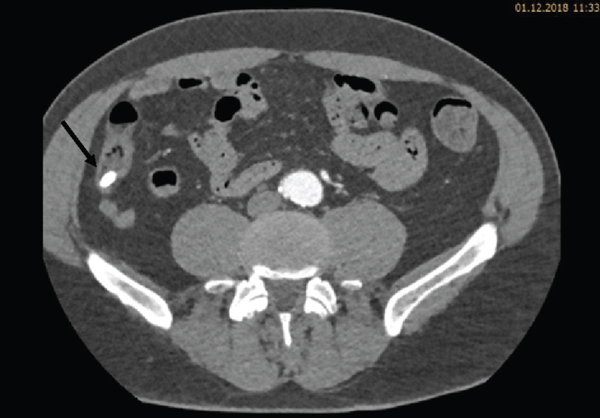

During the ICU stay, the patient’s condition was stable. Bed rest was prescribed, and strict blood pressure control was performed with continuous intravenous infusion of labetalol and urapidil targeting a systolic blood pressure below 120 mmHg. Oral antihypertensive treatment with nebivolol, moxonidine, and amlodipine was started. Continuous labetalol and urapidil infusions were stopped on day three. Due to hypokalemia, potassium chloride tablets were prescribed. Five days after admission, another CT angiography was performed to review the development of the hematoma. The CT scan revealed a reduction of the hematoma. Furthermore, in the arterial phase, a faint hyperdense lesion (max. 348 HU (Hounsfield units), ) was detected in the posterior fundus of the stomach (Figures 1(a)–1(c)). The previously acquired native scan was performed only for the thorax and did not include the stomach; therefore, it was not possible to determine with certainty whether the lesion reflected contrast media extravasation or foreign material. However, due to the intramural hematoma of the descending aorta, the possibility of an aorto-gastric fistula was considered. Additional measurements of hemoglobin were performed to screen for relevant bleeding. As the patient’s hemodynamics as well as hemoglobin levels remained stable, no further investigations (e.g., gastroscopy) were undertaken and our strategy remained expectative. At the same time, we were searching for an alternative clarification of the findings. We found that (1) the patient had ingested two potassium chloride tablets five hours before the CT scan, (2) potassium chloride tablets have radiopaque properties [1, 2], and (3) there were other hyperdense but sharply demarcated structures in the stomach and in the small bowel (density max. 1724 HU) (Figures 2, 3(a), and 3(b)). After putting all available information together, we suggested that the radiopaque lesion in the stomach was caused by the remnants of a degrading potassium chloride tablet ingested by the patient hours before the CT investigation whereas the other potassium chloride tablet ingested at the same time had been propulsed to the small bowel without being degraded in the stomach.

(a)

(b)